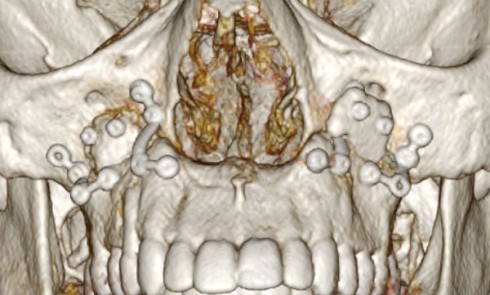

Allogreffes et reconstructions de crête à but préimplantaire Nous avons étudié 100 greffes d’origine allogénique à but préimplantaire réalisées au...

Dans cet article, nous nous intéressons aux indications des allogreffes en chirurgie buccale, en particulier après l’exérèse de kystes des...

Article réservé à nos abonnés Utilisation systématique de greffes allogéniques selon un protocole spécifique

Malgré les prouesses technologiques réalisées par les industriels pour proposer des implants toujours plus courts ou plus étroits, dans le...